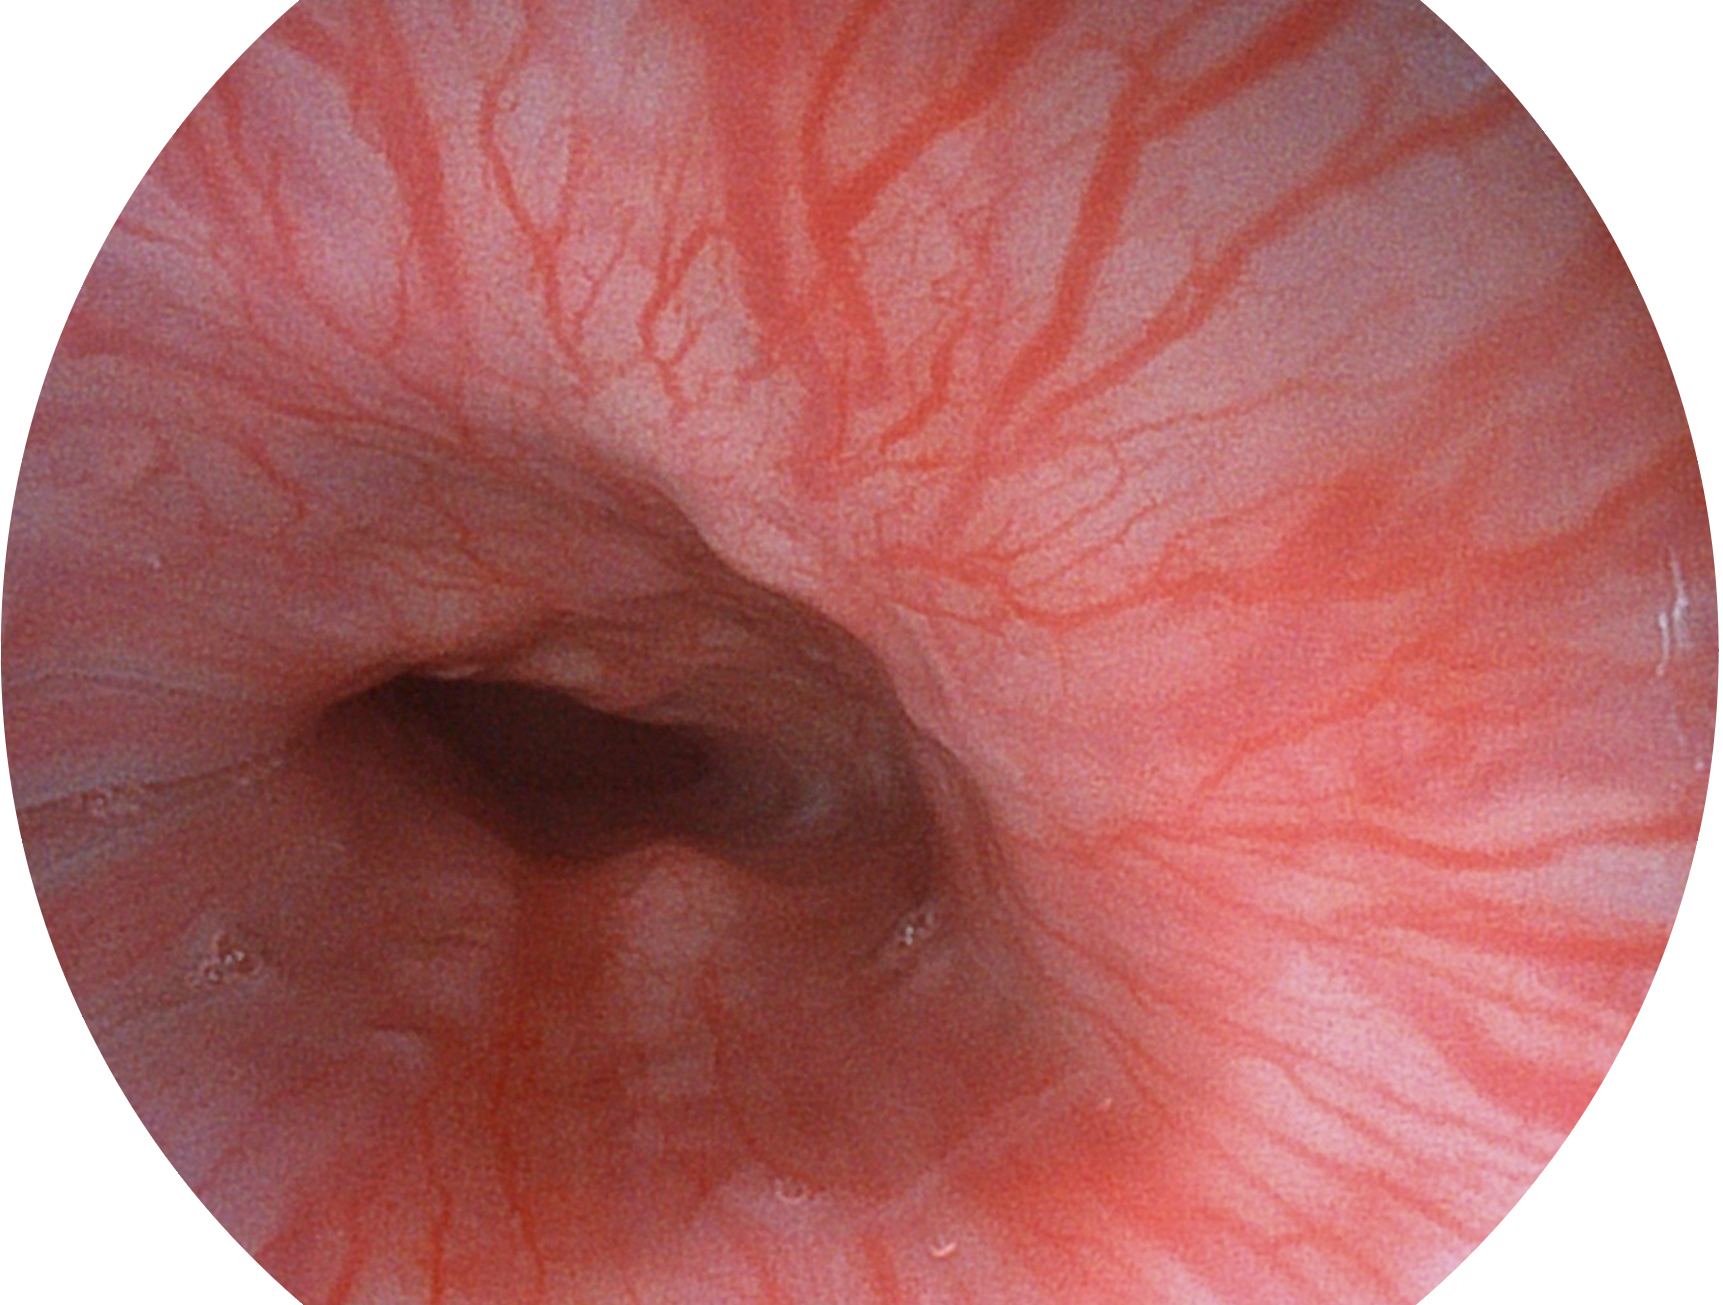

開立新開發(fā)的內(nèi)鏡染色技術(shù),主要是基于多波長LED 光源的開發(fā),VLS-55Q 四波長LED 光源是由四個(gè)不同顏色的LED光按照相應(yīng)照明模式所規(guī)定的特定發(fā)光比例進(jìn)行合束后形成,合束后形成的照明光的光譜由紅光、綠光、藍(lán)光及藍(lán)紫光這四個(gè)不同的波段范圍構(gòu)成。具有更高光譜自由度,通過光譜比例的控制,實(shí)現(xiàn)了聚譜成像技術(shù),英文全稱為“Spectral Focused Imaging, SFI”,縮寫為“SFI”和光電復(fù)合染色成像技術(shù),英文全稱為“Versatile Intelligent Staining Technology, VIST”,縮寫為“VIST”。